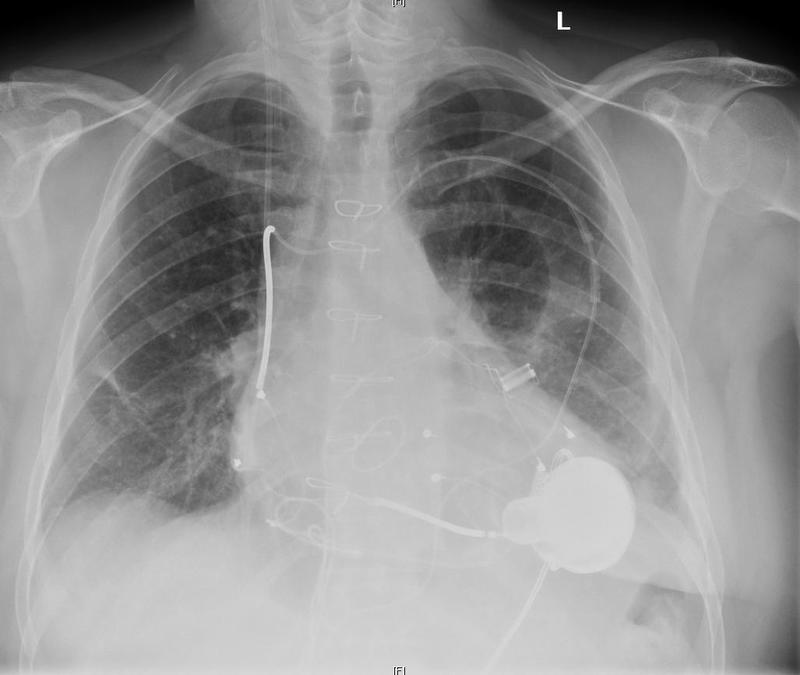

Sahyadri Super Speciality Hospital, Deccan recently conducted a rare and high risk left ventricular assist device implantation (LVAD) procedure on a 22-year-old Yemeni National who was suffering from end stage heart failure.

Explaining the case Dr. Manoj Durairaj, Programme Director, Department of Heart Transplantation Sahyadri Hospitals said, "When this patient came to us four months back he was suffering from breathlessness. Investigations revealed that the main pumping chamber of his heart was affected which resulted in end stage heart failure. We didn't have many options before us and we decided to go for LVAD implantation procedure as the patient was very sick. In such cases heart transplant may be an option, but being an overseas patient the long waiting period could have virtually shut any hopes." Dr. Durairaj added that the Left Ventricular Assist Device takes over the function of the main pumping chamber of the heart, the left ventricle.

This option is chosen for patients who have end stage heart failure when all other treatment options have failed. It can be a permanent treatment (Destination Therapy) or can used as a Bridge to Heart Transplant. The procedure involves performing open heart surgery on a heart lung machine. The surgery is challenging due to the fact that the patients have advanced heart failure, so managing the patient during and after surgery requires well-trained doctors and other health care providers. The implanted machine is controlled from outside initially so that the programming has to perfect before discharge.

The machine which is implanted runs on a miniature mobile battery control unit which has to be carried by the patient and required recharging every 8-12 hours. The patient and the care givers are given training on managing this unit and taking care of the batteries. The patient will also have to be on blood thinner tablets.